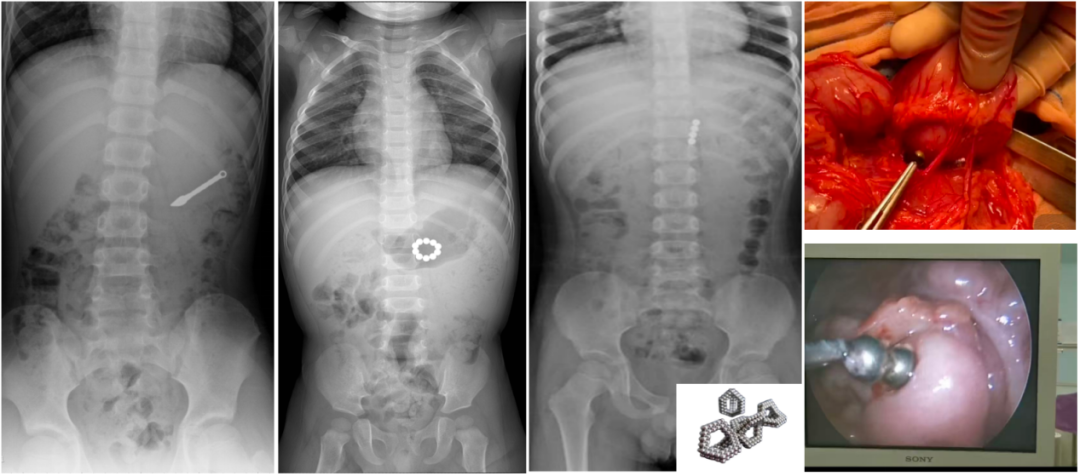

X线下异物(左1玩具、左2磁珠、左3巴克球)、剖腹手术取出消化道异物(右1上)腹腔镜下异物取出(右1下)